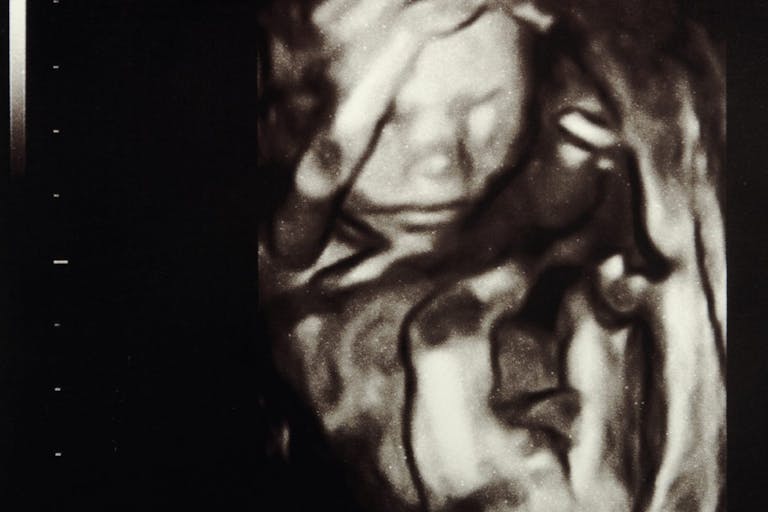

Would this woman have aborted if she’d known how developed her baby was? Would seeing her child on a sonogram have changed her mind? We will never know. But we do know that many women have abortions without realizing how developed their babies are, and that abortion facility workers have lied to women about fetal development.